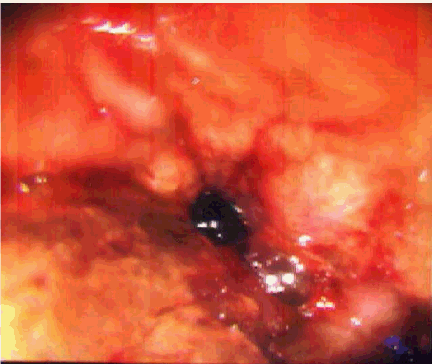

Examination was remarkable only for auscultatory wheeze over the right mid zone anteriorly and right base posteriorly. Hematologic investigations showed microcytic anemia with hemoglobin of 11.1 g/dL and mean corpuscular volume, (MCV) of 73 fL. Chest radiograph revealed a large left hiatal hernia but was otherwise unremarkable. A contrast chest computed tomography (CT) scan confirmed the hiatal hernia but was devoid of any other abnormality. Fiberoptic bronchoscopy done within 24 hours revealed that the tracheal and bronchial mucosa was erythematous and edematous. The mucosa at the bifurcation of the right middle and lower lobe and in the right lower lobe was most affected and appeared corrugated, ulcerated, friable and bled easily (Figure 1). The area was lavaged and thick brownish secretions were suctioned. Bronchial biopsy at the level of right middle and lower lobe carina and from the right lower lobe revealed features of mucosal burn with edema and inflammation and stained positive for iron with prussian blue stain (Figure 2, 3).

Figure 2: Prussian Blue stain for iron on bronchial biopsy was positive.